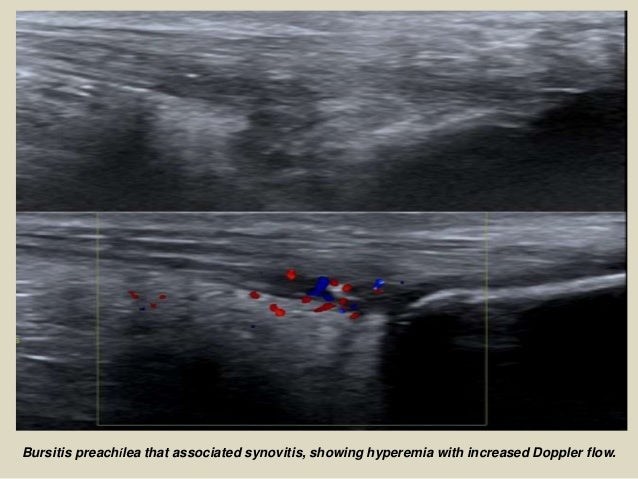

Bursitis preachílea that associated synovitis, showing hyperemia with increased Doppler flow.

29. 29. Bursitis preachílea that associated synovitis, showing hyperemia with increased Doppler flow.